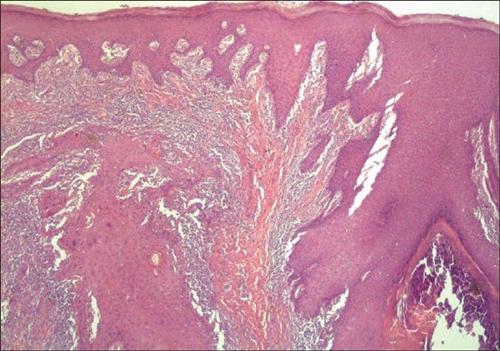

疣状癌1948年由首先报告本病,为高角质化鳞状细胞癌,本病的诊断需靠此瘤的临床、镜下形态以及生物学行为判断。肿瘤生长缓慢,最初呈外生性疣状和蕈样肿瘤,最后侵入深部组织。很多人久治不愈,不是因为治不好,而是不了解,下面跟大家介绍下外阴疣状癌症状?。

第二:生殖器肛门区疣状癌(verrucous carcinoma of the genitoanal region)亦称Buschke-Loewenstein巨大尖锐湿疣。1925年由Buschke和Loewenstein首先报告,大多数病例由HPV6或HPV11所引起,本病占阴茎恶性肿瘤之5%~25%。临床上呈菜花样乳头瘤样增生,最常见于男性龟头和未环切的包皮处,最后侵入尿道。也见于女阴及肛门区,损害可形成溃疡及漏管。常散发臭味。

相关图片